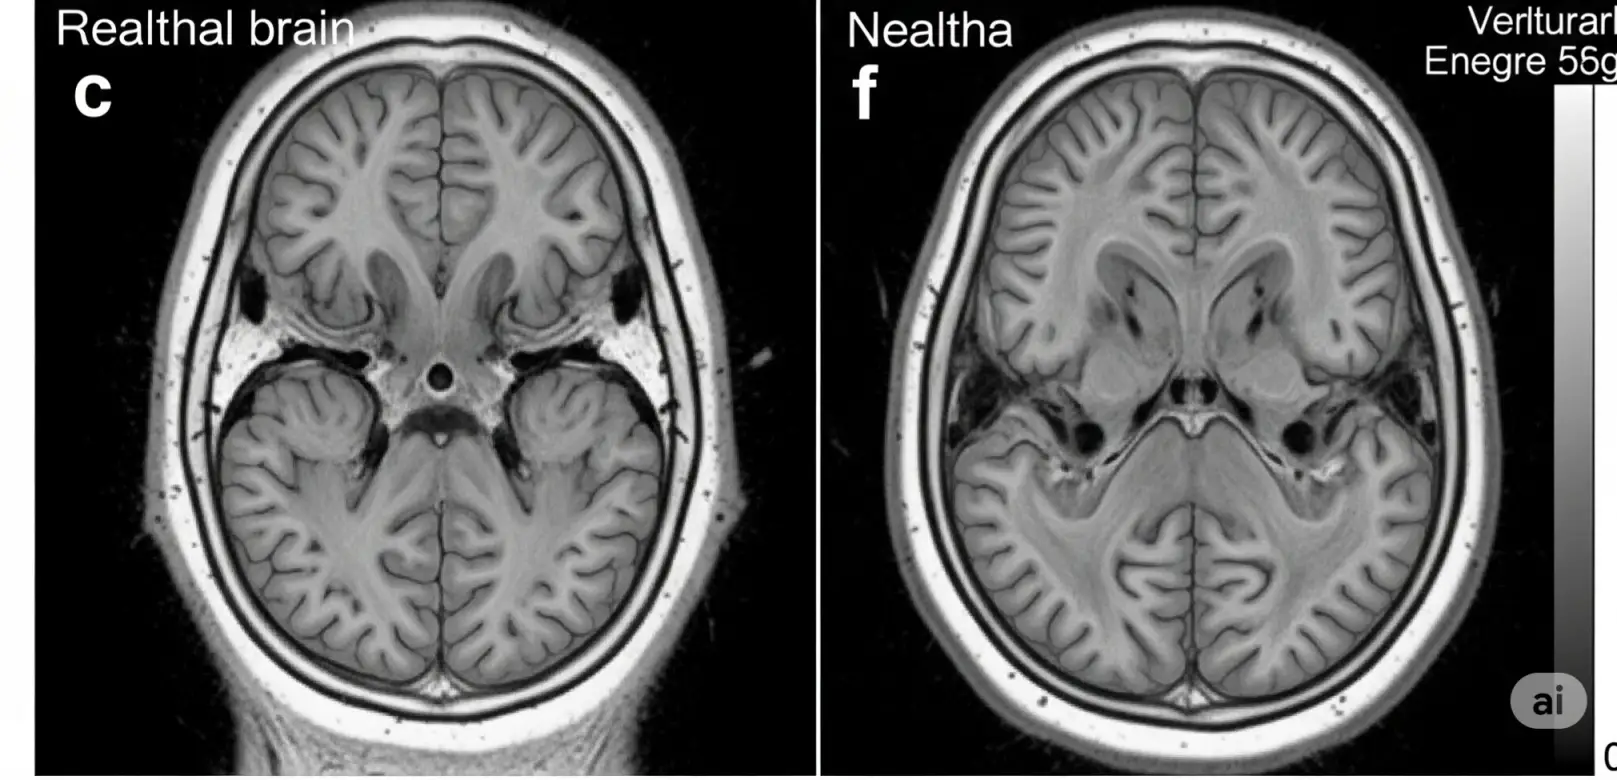

① 뇌 앞부분에 문제가 생기는 치매예요

전두엽과 측두엽은 감정, 언어, 판단력을 담당하는 뇌의 앞쪽 부분이에요.

이 부위에 신경세포가 죽거나 위축되면, 말이 어눌해지고 성격이 바뀌고, 감정 표현도 둔해지죠.

전두엽이 심하게 위축되면서 보행에도 문제가 생겼어요.